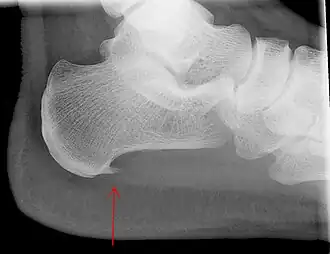

Fasciitis plantaris is een overbelastingsletsel. Veelvuldige belasting van de fascie kan leiden tot microscheurtjes, wat eventueel kan leiden tot ontsteking en degeneratie van het bindweefsel (collageen) in de fascie. De term fasci-itis doet voorkomen dat we hier te maken hebben met een ontstekingsproces (de uitgang -itis wijst op een ontsteking). Hoewel er aanvankelijk inderdaad een ontstekingsproces plaatsvindt, wat zich uit in o.a. roodheid, zwelling en pijn, evolueert deze aandoening snel naar een degeneratief proces. We spreken dan van een tendinose in plaats van een tendinitis. Als de aandoening langdurig bestaat treedt er vaak een verkalking op in de aanhechting van de fascie aan het hielbeen, die de naam 'hielspoor' draagt. Deze is echter niet de oorzaak van de pijn of de ziekte maar een gevolg van de ontstekingsprocessen.

- hielspoor